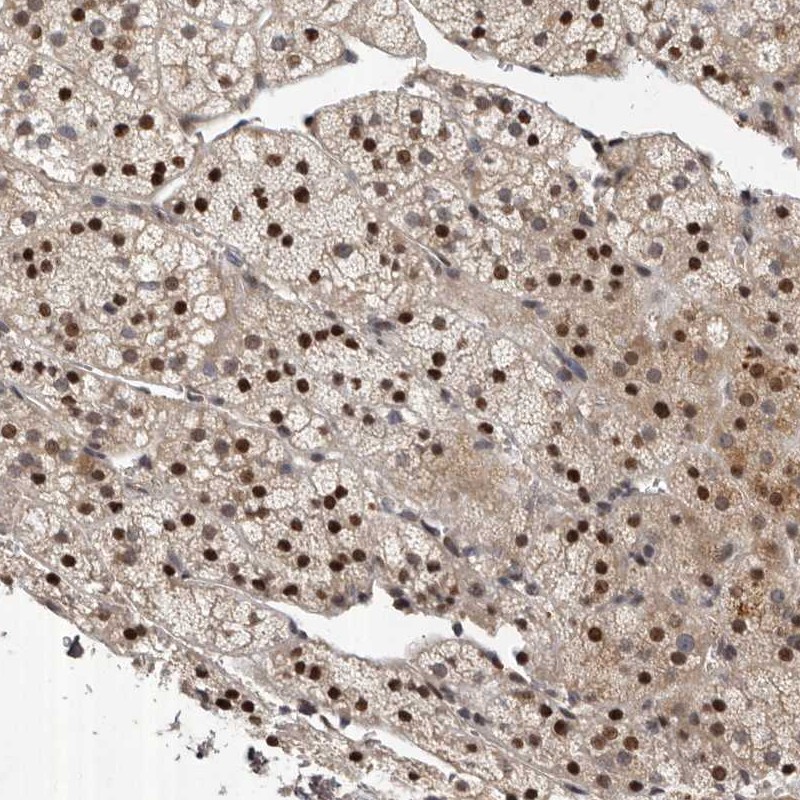

Immunohistochemical staining of human adrenal gland shows strong nuclear positivity in cortical cells.